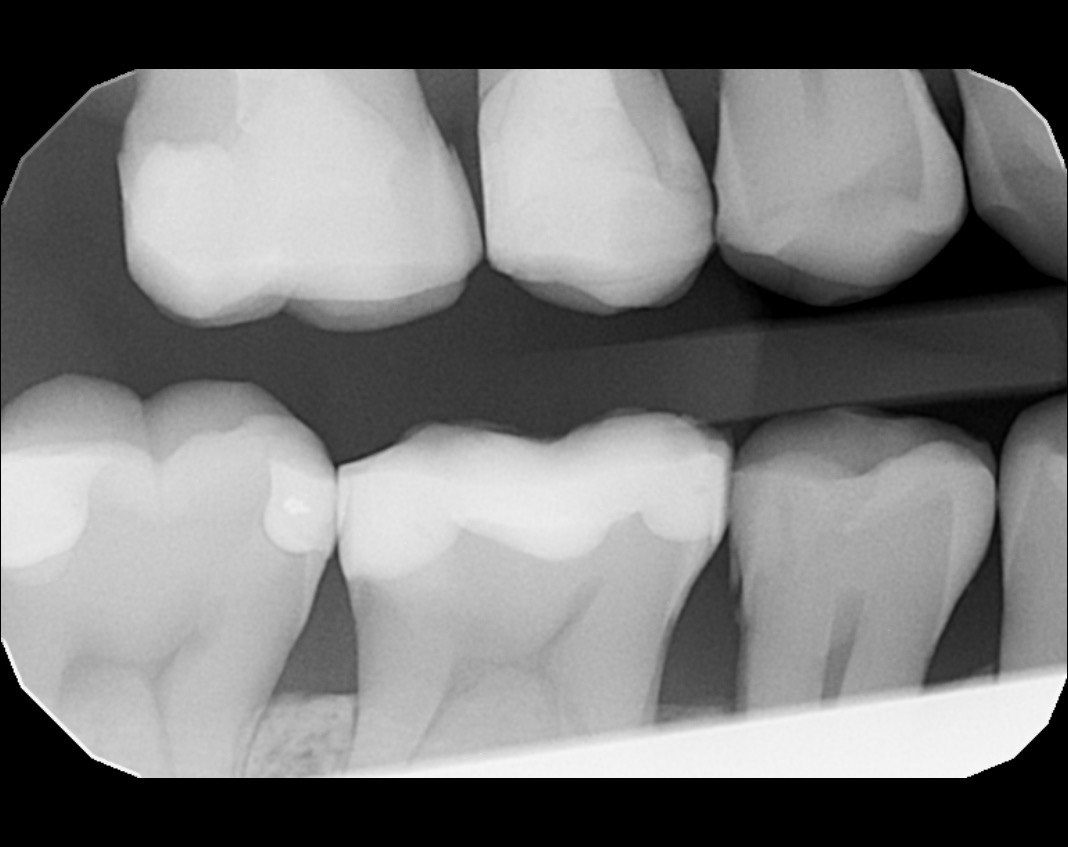

Question 11: Which materials cannot be seen in the print of the X ray?

Question 12: What option cannot be selected for the following X ray?

Question 13: What option cannot be selected for the following X ray?

Question 14: Which surface shows overhang restoration?

Question 15: Which surface shows overhang in the restoration?

Question 16: Which surface shows overhang?

Question 17: Which surface shows overhang?

Question 18: Which surface shows overhang?

Question 19: Which option can be chosen for the tooth # 3.6?

Question 20: which tooth shows defective resotration?